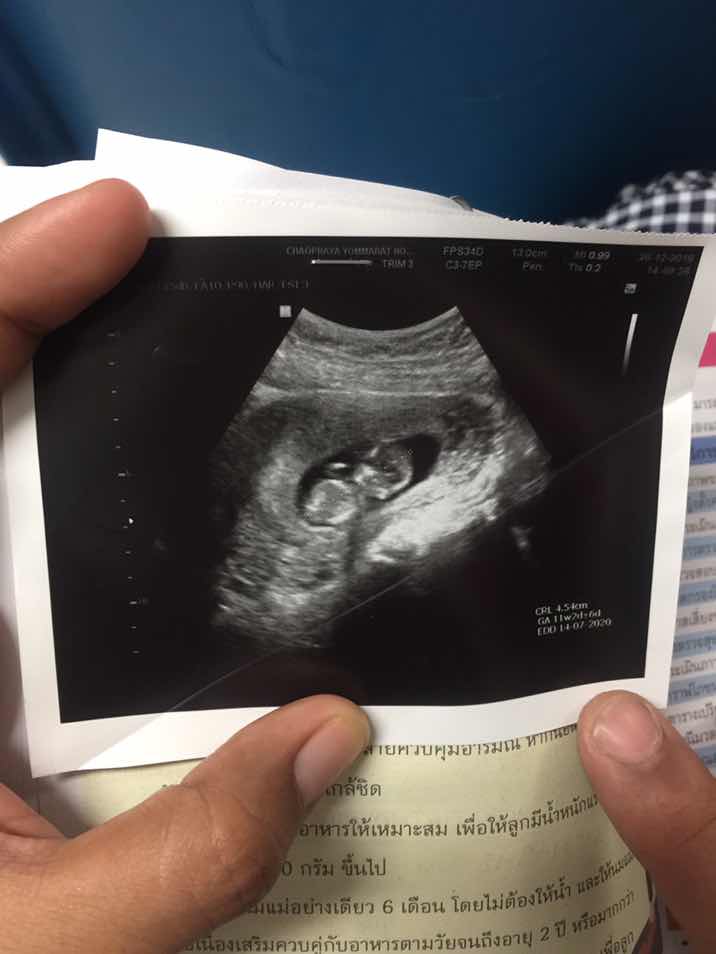

11w4d ค่ะ